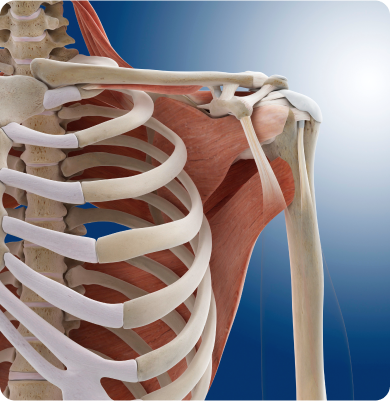

어깨 관절을 둘러싼 관절막이 퇴행성 변화를 일으키면서 염증을 유발하는 질환

주로 40~60대에 발생하며 어깨를 오래 사용하지 않거나 움직임이 제한될 때 관절이 굳어 생기거나 당뇨병 등 기저질환이 원인이 됩니다.

어깨 관절을 감싸고 있는 회전근개 힘줄이 손상되거나 찢어지는 질환

어깨 관절의 안정성을 유지해주는 연골조직인 관절와순이 손상되거나 찢어지는 질환

어깨 관절에 반복적으로 스트레스가 가해지는 스포츠 활동, 팔을 머리 위로 던지는 동작, 낙상이나 외상 등 급격한 충격 그리고 나이에 따른 조직 퇴행으로 발생합니다.